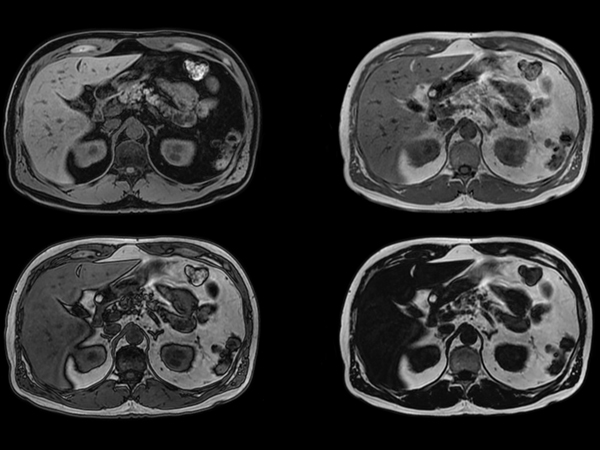

Total Torso imaging - MultiVane XD